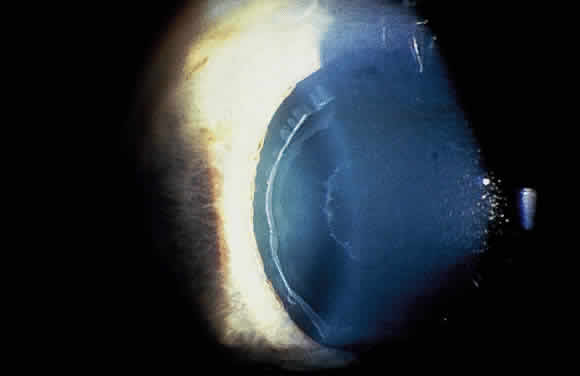

Accumulation of exfoliative material may be detected histopathologically throughout the anterior segment to include the lens, iris, trabecular structures, conjunctiva, ciliary body, and zonules. The deposition of fibrillar eosinophilic material on the anterior lens capsule is the classic histopathologic feature of XFS (Fig. 9). Ultrastructural studies also indicate some degree of actual exfoliative changes or peeling of the anterior lens capsule74 (Figs. 10 and 11). In addition, Ashton and associates describe a degenerative band containing exfoliative material within the inner half of the lens capsule.5 Bertelsen and coworkers independently noted projection of coarse fibrils from the lens surface into the deep portion of the lens capsule to form an amorphous layer of the lens capsule between the lens epithelium and normal lens capsule.6 Thus, studies indicate that exfoliative material accumulates on the anterior lens surface but also that the lens capsule itself may be involved, and that the underlying epithelial layer may at least partially contribute to the production of the exfoliative material.

Fig. 9. Deposition of fibrillar eosinophilic material on anterior lens capsule in exfoliation syndrome (PAS, × 250). (Courtesy of Dr. Marilyn C. Kincaid and Armed Forces Institute of Pathology, Washington, DC)